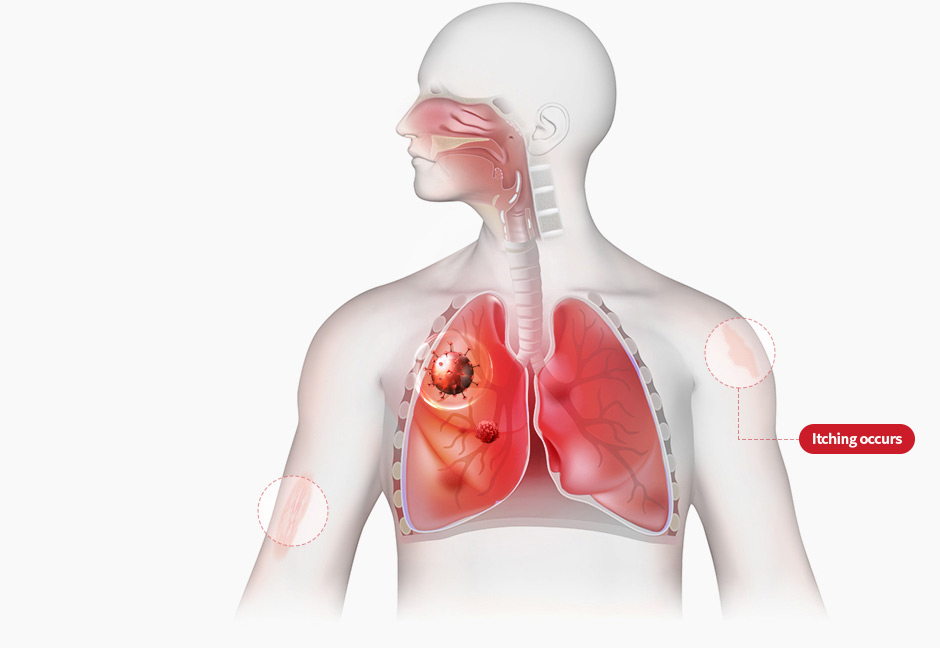

In Korean medicine, itching is thought to arise when “wind-heat” remains in the body while skin pores fail to open adequately. Removing wind-heat and fully opening the pores—gweo-pung cheong-yeol—is the basic principle for treating pruritus. Pyunkang-tang aims to strengthen the lungs and expel toxins and wastes that accumulate beneath the skin, which is governed by the lungs, cleansing the skin and treating itch at its root.

Through the lung-cleansing (Cheongpye) action of Pyunkang-tang, accumulated heat in the lungs is lowered and vitality is replenished. Under the guidance of the lungs—which handle 95% of the body's respiration—the skin, the body's 'minor respiratory organ,' opens its sweat and hair pores to release toxins and waste.

STEP 2

Normalize lung function

with Pyunkang-tang

(Lung function gradually recovers, enabling skin respiration)

STEP 2

Normalize lung function

with Pyunkang-tang

(Lung function gradually recovers, enabling skin respiration)